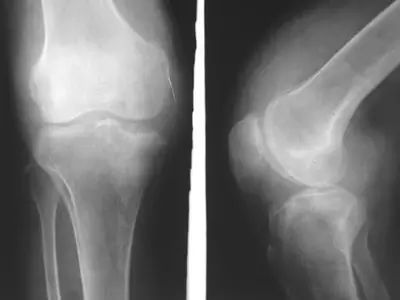

走出来的滑膜炎!

前不久,杭州的刘先生想通过暴走减肥,每天走的步数都在15000以上,没想到,不到一星期,就患上了膝关节滑膜炎!医生说,刘先生是走得太多了!属于过度运动,已经伤害到了身体!

日行2万步,膝关节积液!

张阿姨今年50多岁,平时爱好锻炼身体的她,经常到附近公园散步,基本上每天两万步打底。没想到,这种追求健康的方式给她带来大麻烦。正是因为走路太多,对膝盖产生了损伤,时间长了,原本应该起到润滑关节作用的关节腔液越来越多,这才形成了积液。